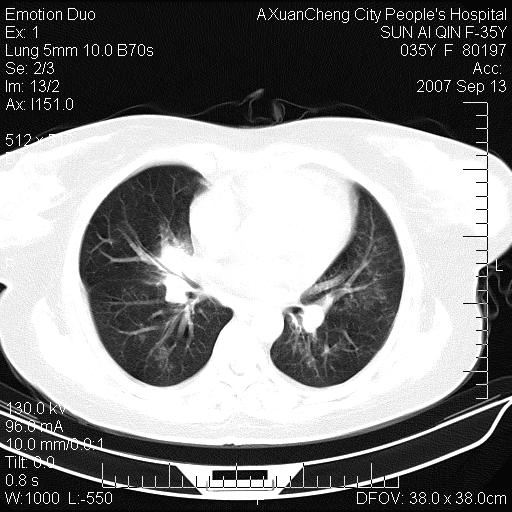

以下是引用天南地北在2007-9-13 13:43:00的发言:[br]考虑双肺、肺门侵润

以下是引用ydx_74在2007-9-13 15:42:00的发言:[br]仅看片,考虑右上肺癌并双肺转移,结合病史,考虑肺门、肺内淋巴侵润

以下是引用同在2007-9-13 15:08:00的发言:[br]支持肺门及双肺侵润.